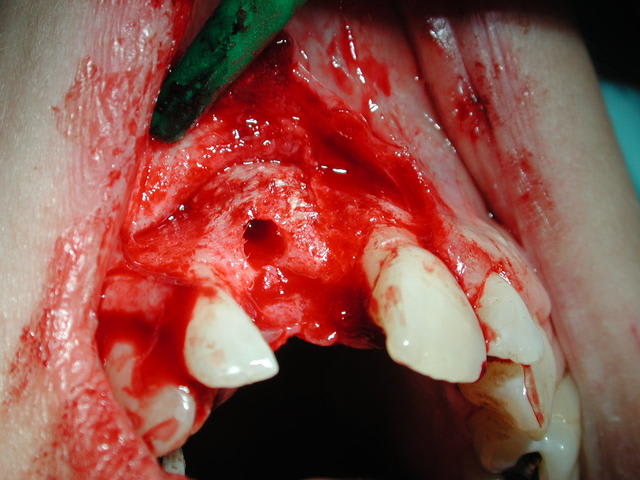

Sur photo 4555 : greffon allogène fixé par 1 ou 2 vis d'ostéosynthèse : immobilisation absolue obligatoire .

Sur photo 4570 : lambeau mucopériosté pour abord de la zone vestibulaire puis épaisseur partielle pour gagner de l'élasticité et recouvrir complètement le surplus de volume causé par le greffon + les membranes de PRF qui protègent ce greffon.

Sur photo 1401 : autre patient lors de la réouverture à 6 mois : l'os allogène est rescussité : n'ayons pas peur des mots !!!

Sur photo 1411 : le greffon est parfaitement intégré et le forage ne sépare pas le greffon de l'os nourricier palatin ; ce qui était ma petite angoisse la première fois que j'ai fait çà .